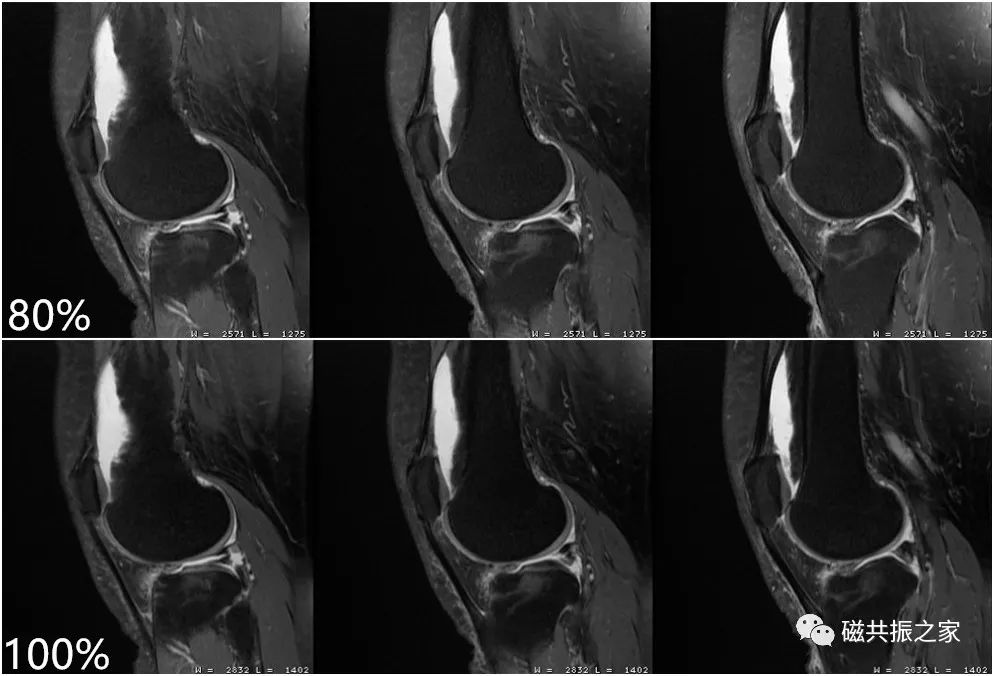

MRI的信号主要来自于水和脂肪中的氢质子,虽然较强的压脂程度可突出某些组织间的对比,但更多的脂肪被抑制掉,图像的SNR会下降,图像会更“黑”,则不利于我们做更高分辨率的图像。在进行膝关节的小体素扫描时,使用部分压脂则可以保证图像足够的信噪比。如上图的压脂程度为80%,下图的压脂为100% 。